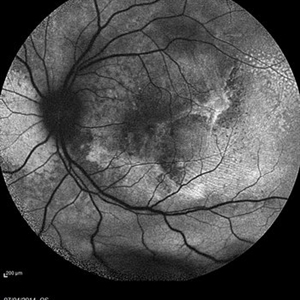

Multifocal Exudative Detachments Due to VKH

May 14 2014 by Avris Romario Diparaja Siahaan

Blue auto fluorescence fundus photograph a 38-year-old man with multifocal CSR and inferior exudative retinal detachment on both eyes (Harada Syndrome). This patient has underwent a photocoagulation laser on both eyes.

Photographer: Avris Romario Diparaja Siahaan, Klinik Mata Nusantara

Imaging device: Heidelberg HRA + OCT Spectralis

Condition/keywords: fundus autofluorescence (FAF), multifocal central serous chorioretinopathy (CSCR)